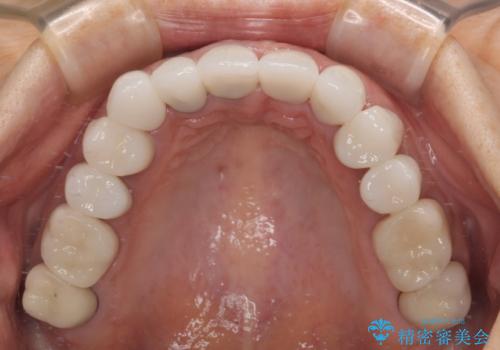

色調が統一されるだけでなく、歯肉ラインに見えていた茶色の境目も綺麗に改善されました。